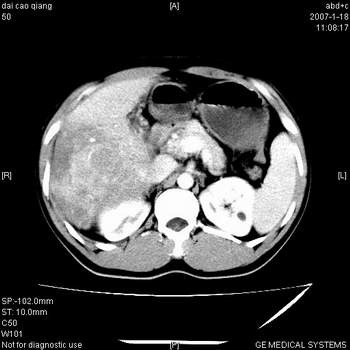

符合巨块型肝癌表现:

1、平扫低密度,增强后表现为快进快出。

2、动脉期可见迂曲的动脉供血血管

3、并可见门静脉右支癌栓形成

4、可见假包膜

5、腹主动脉旁结节影,考虑肿大淋巴结。

肝右叶巨大不均匀低密度肿块,前缘有假包膜,增强明显的呈快进快出表现,门脉右支有癌栓,病人虽然年轻但还是首先考虑肝右叶巨块形肝癌,病人血象高只能说有合并感染。不支持肝脓肿。